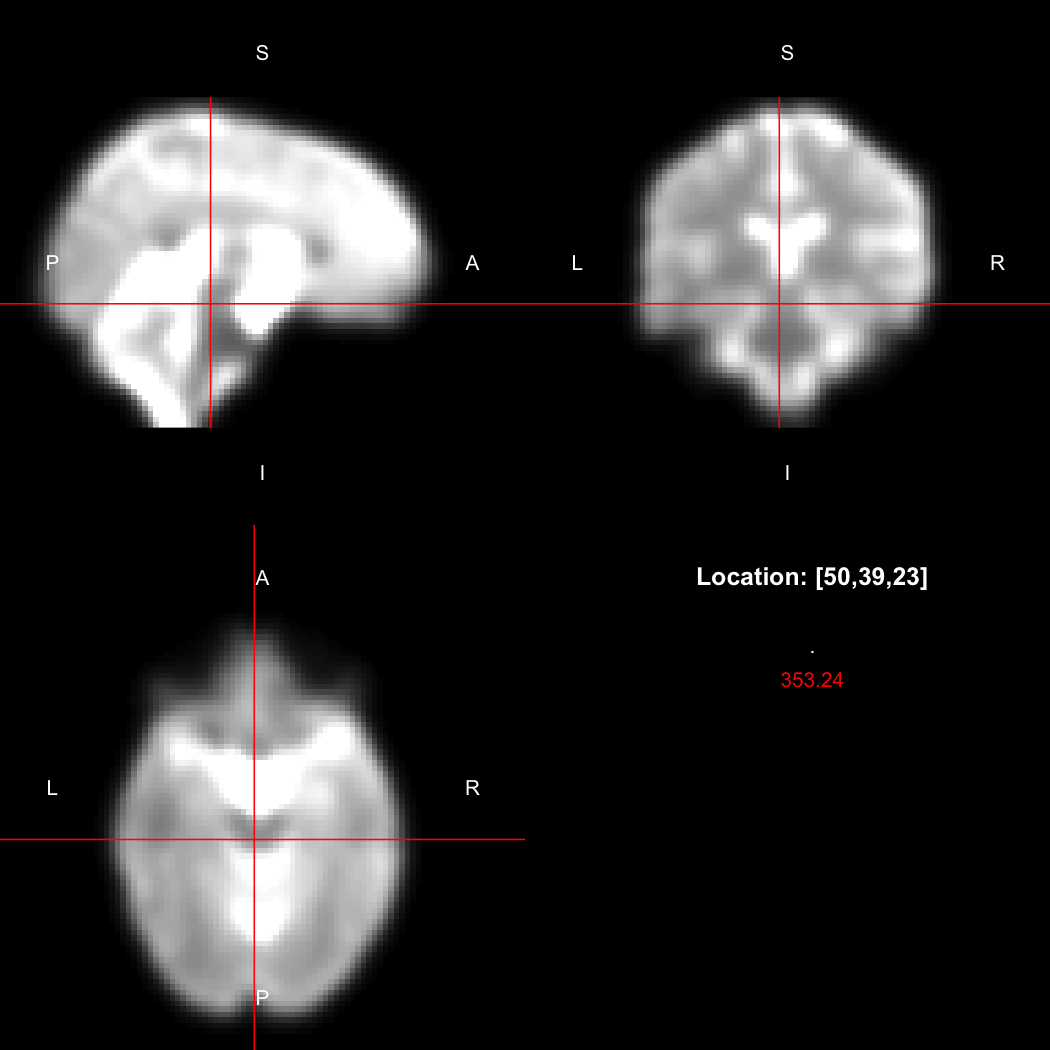

image %>% kernel_sphere(radius=3) %>% dilate() %>% subtract(image) %>% view()

## Setting window to (0, 60)

plot of chunk dilate

This example sets up a spherical kernel of radius 3 mm, dilates the image with it, and then subtracts the original image from the result to leave just the outer edge of the imaged object.